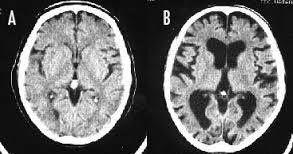

>>33 どうだろう、副流煙ではわからないけど 長期の喫煙で大脳皮質が薄くなって認知機能が低下するのはガチらしい 画像の左(A)は正常の脳で右(B)は喫煙者の脳 喫煙者の脳は萎縮して隙間だらけになってる 詳しくはリンク先参照

--- 「喫煙者の脳」やはり異変が起きていた(石田雅彦) - Yahoo!ニュース ---

タバコを吸うと脳がすっきりするのは真っ赤な嘘だ。研究によれば喫煙者の脳では明らかに異常が起きている。認知機能も低下し、大脳皮質が元に戻るのには25年もかかる。一刻も早くタバコなど止めたほうがいい。